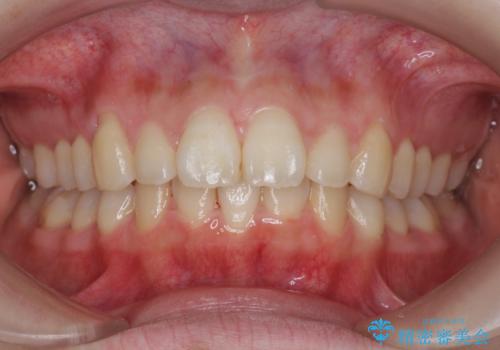

マウスピースで出っ歯感の改善

- 上の前歯が出ている感じを治したい、と矯正治療を希望され来院されました。

上顎歯列の突出感を改善すべくIPRを行い、下顎歯列を小さくすることで前歯の角度を大きく是正します、。

下顎歯列は元々前歯が1本少なく小さなアーチでしたが、下顎に合わせ上顎歯列もIPRを行い小さくすることで出っ歯感を大きく改善することが出来ました。